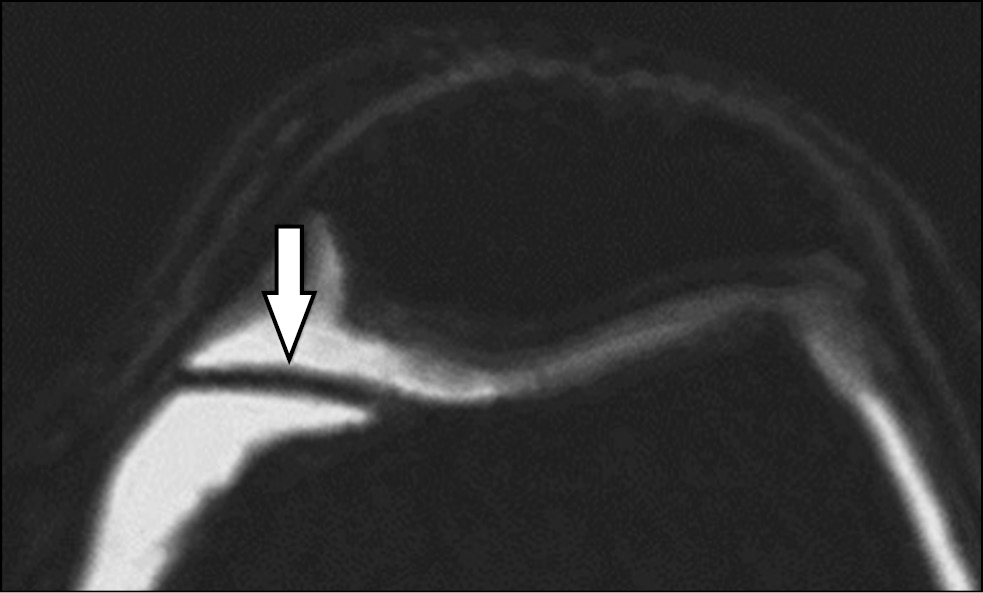

Всем пациентам перед назначением УЗИ было выполнено МРТ коленного сустава на аппарате Ingenia 1.5 Т (Philips, Нидерланды) (рис. 1). МПСС выглядит как полоса низкой интенсивности как на Т1, так и на Т2 взвешенных изображениях, расположенной перед медиальным мыщелком бедренной кости. Она находится непосредственно за жировой складкой треугольной формы. Медиопателлярная пластинка имеет низкую интенсивность сигнала на взвешенных изображениях T1 и T2, ее можно оптимально визуализировать с помощью взвешенных изображений T2 в аксиальной и сагиттальной плоскостях, взвешенные изображения T2 могут быть выполнены с подавлением жира или без него. У всех пациентов проведена оценка типа складки в соответствии с классификацией J. Sakakibara [16].

Рис. 1. Полученная с помощью магнитно-резонансной томографии картина медиопателлярной синовиальной складки

Fig. 1. A picture of the mediopatellar synovial fold obtained using magnetic resonance imaging